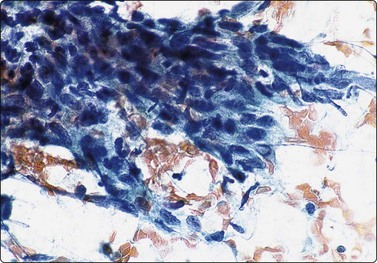

Myoepithelial adenoma22,126,127 may be of spindle cell (Fig. 4.46A), plasmacytoid (Fig. 4.46B) or epithelioid type. This tumor may not be distinguishable from a cellular pleomorphic adenoma in which a solid focus of spindle or plasmacytoid cells without specific stroma has been selectively sampled. The spindle cell type can also be confused with a benign soft tissue tumor. Distinction of the plasmacytoid type from malignant myoepithelioma can be difficult since anisokaryosis and mild nuclear atypia can occur. Mitotic figures and necrosis suggest malignancy. Positive nuclear staining for p63 supports a diagnosis of myoepithelial adenoma (Fig. 4.46C).

image image image

Fig. 4.46 Myoepithelial adenoma

(A) Spindle cell type; the pattern of bland spindle cells could be mistaken for a benign soft tissue tumor (Pap, HP); (B) Plasmacytoid type; poorly cohesive cells with abundant cytoplasm and eccentric nuclei. The nuclear atypica in this case caused some concern (MGG, HP); (C) Tissue section corresponding to (B), immunostaining for p63 (IP).